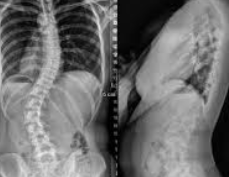

척추측만증은 엑스레이나 자기 공명 영상(MRI) 검사를 통해 진단할 수 있으며, 척추의 만곡이 10도 이상일 때 측만증으로 진단됩니다. 치료 방법은 증상의 정도와 환자의 나이, 만곡의 진행 속도 등에 따라 달라질 수 있습니다. 경미한 경우에는 정기적인 관찰과 운동 요법으로 관리할 수 있으며, 심한 경우에는 보조기 착용이나 수술적 치료가 필요할 수 있습니다.

1. 관찰: 경미한 척추측만증의 경우, 특별한 치료 없이 정기적인 의사 상담과 X-선 검사로 진행 상황을 추적하는 것이 충분할 수 있습니다. 이는 만곡이 20도 미만일 때 주로 고려됩니다.

2. 보조기 착용: 만곡이 20도에서 40도 사이이며, 아직 성장 기간이 남아 있는 환자에게는 보조기를 착용하여 만곡의 진행을 막고 교정하는 방법이 사용됩니다. 보조기는 척추의 균형을 유지하고 추가적인 만곡을 방지하는 데 도움을 줄 수 있습니다.

3. 수술적 치료: 만곡이 심하거나 보조기 착용으로 개선되지 않는 경우, 수술적 치료가 필요할 수 있습니다. 수술은 척추의 만곡을 교정하고 고정시키는 것을 목표로 하며, 이는 주로 40도 이상의 만곡에 적용됩니다.